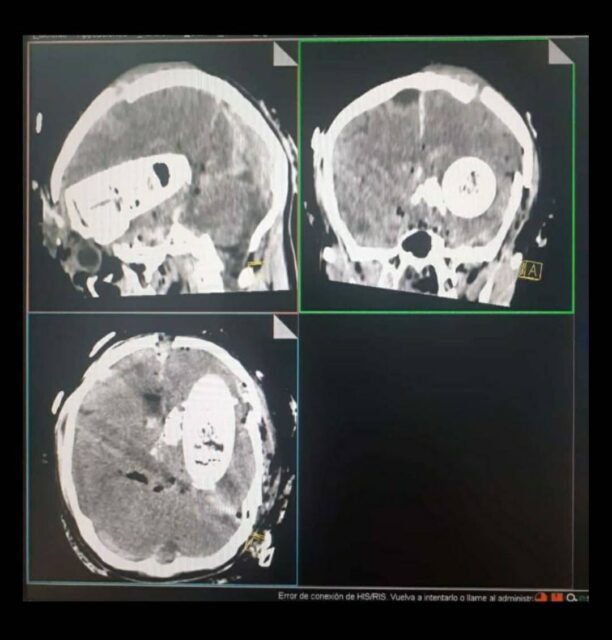

これに対し、人権団体連盟はTwitterで「バイロンの死は爆発物の扱いによるものではない。国家警察こそが催涙弾を投げ使用している。真実と正義、そして補償を要求する」と反論した。また、エクアドル・アマゾニア先住民族連合(Confederación de Nacionalidades Indígenas de la Amazonía Ecuatoriana:CONFENIAE)は声明で、「治安部隊の不当かつ過剰な暴力と抗議者に対する直接射撃」を非難し、人権団体の介入を求めた。さらに「国家警察の手はバイロンの血で汚れている」と述べ、彼を兄弟のように見なしていることを表明した。声明では、頭蓋骨に埋まった催涙弾のCT写真も公開された。

これに対して、上述の通り内務大臣パトリシオ・カリジョは記者会見で、事件の責任は抗議者にあると主張し、「爆発物、手製の武器、カービン銃のような武器を所持していた。彼らが市民や警察に攻撃を開始した」と述べた。しかしながら、国際人権団体アムネスティ・インターナショナル(Amnistía Internacional)アメリカ担当ディレクターのエリカ・ゲバラ・ロサス(Erika Guevara Rosas)は、証言とデジタル証拠の分析を踏まえ、バイロンの死は「警察官を含む治安部隊による過剰な武力行使が原因であり、検察総長が速やかに捜査すべきである」とした。同団体によれば、催涙ガスの手榴弾をエクアドル警察が「直接かつ至近距離から投擲」したことでプヨ中心部、タルキ通り(Avenida Tarqui)とアントゥリオス通り(Calle de los Anturios)の角でバイロン・グアタトゥカ(Byron Guatatuca)を死に追いやった。